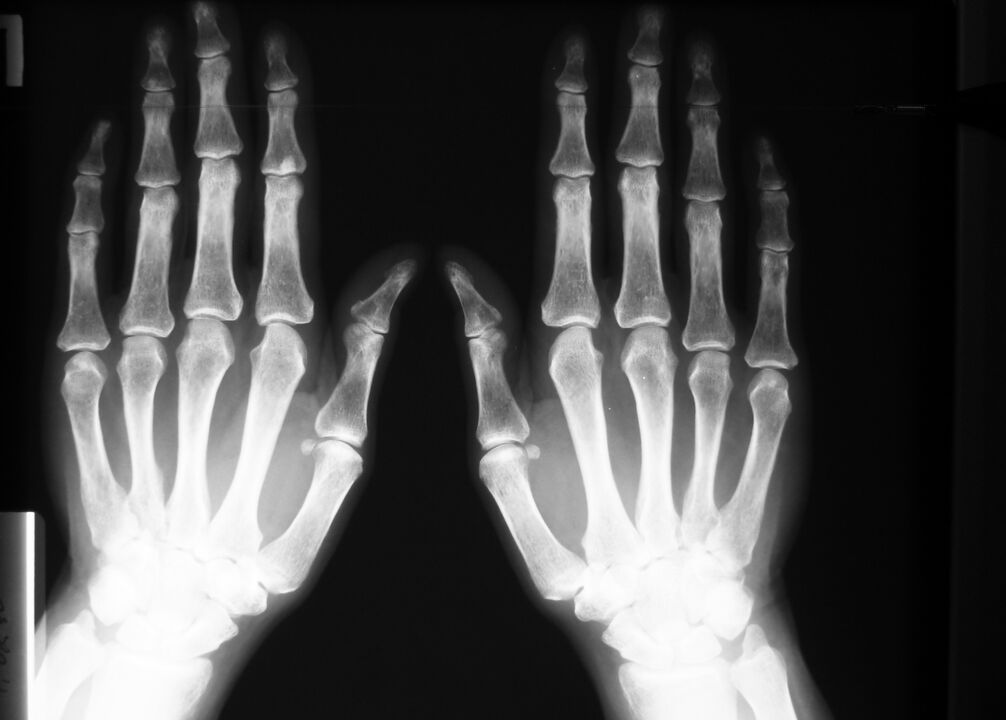

Dans les maladies dégénératives et les blessures – modifications des articulations : tissu osseux et cartilage visibles sur les radiographies ou les résultats de tomodensitométrie.

Même en cas de tendinite, de déchirures ligamentaires ou musculaires, l'IRM fournit une image complète des modifications des tissus mous.